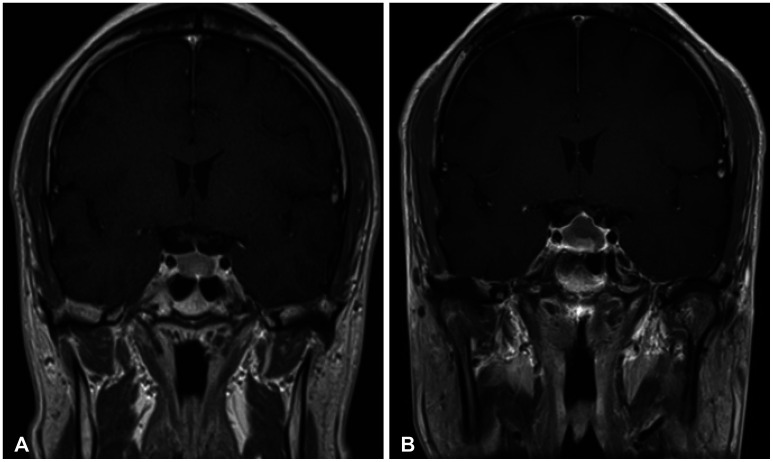

Results: PI size increased in 33 of 245 patients. For the remaining 212 patients, PI size decreased or stayed unchanged. Of the 33 patients with PI size progression, ten underwent surgery. Stalk deviation (p<0.001) and lesion enhancement (p=0.001) were significantly more observed in those with PI size progression than in those without PI size progression. MRI morphological factors were not related to changes in PI size in the presumptive Rathke's cleft cyst group. In the presumptive pituitary adenoma group, absence of tumor enhancement (p<0.001) and stalk deviation (p<0.001) were significantly associated with tumor reduction and progression, respectively.

Conclusion: Our findings support an additional guideline for patients with asymptomatic non-functional PI without stalk deviation and enhancement. For these patients, the clinical and neuroradiological follow-up periods could be reduced.